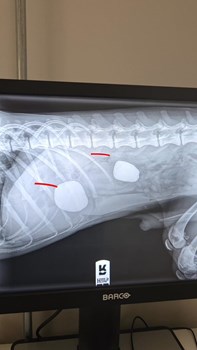

Herning Svømmehal informerer om et stævne i 50m-hallen, men der vil stadig være plads i andre bassiner. Herning Løve Apotek anbefaler produkter med salt til at lindre vejrtrækningsproblemer. Vestergades Blomster tilbyder en traditionel rundpyntet krans. Dyrehospitalet Heden deler historien om en Springer Spaniel, der gentagne gange har spist sten.

Se hele opslaget på HV Care/Kim Schmidt/Henrik P Hornstrups FacebooksideManfred er en ung og meget sød Springer Spaniel på 9 måneder… med en lidt for stor forkærlighed for at spise sten 🙈 I slutningen af januar kom han ind til os, da han havde tabt sig og var begyndt a...